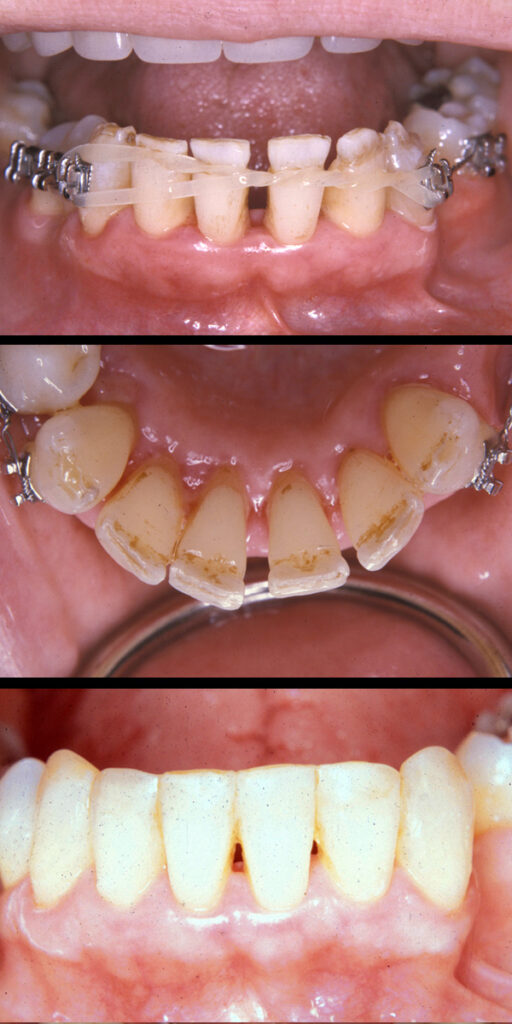

Periodontal Tooth Movement (Limited Orthodontics):

Bone loss (as a result of periodontal disease) can cause your teeth to shift. Shifting teeth can be unsightly, difficult to chew with, loose, harder to clean, and sometimes harder to restore.

Some of these situations are easily corrected with periodontal tooth movement i.e. minor orthodontics. Treatment time can take as little as 3-6 months and provide both you and your doctor with a healthy and cosmetic foundation from which to complete your restorative care.

Dr. Sterrett received comprehensive training in his graduate program on this type of therapy and he would be glad to share with you his thoughts about your case and answer any questions you may have.